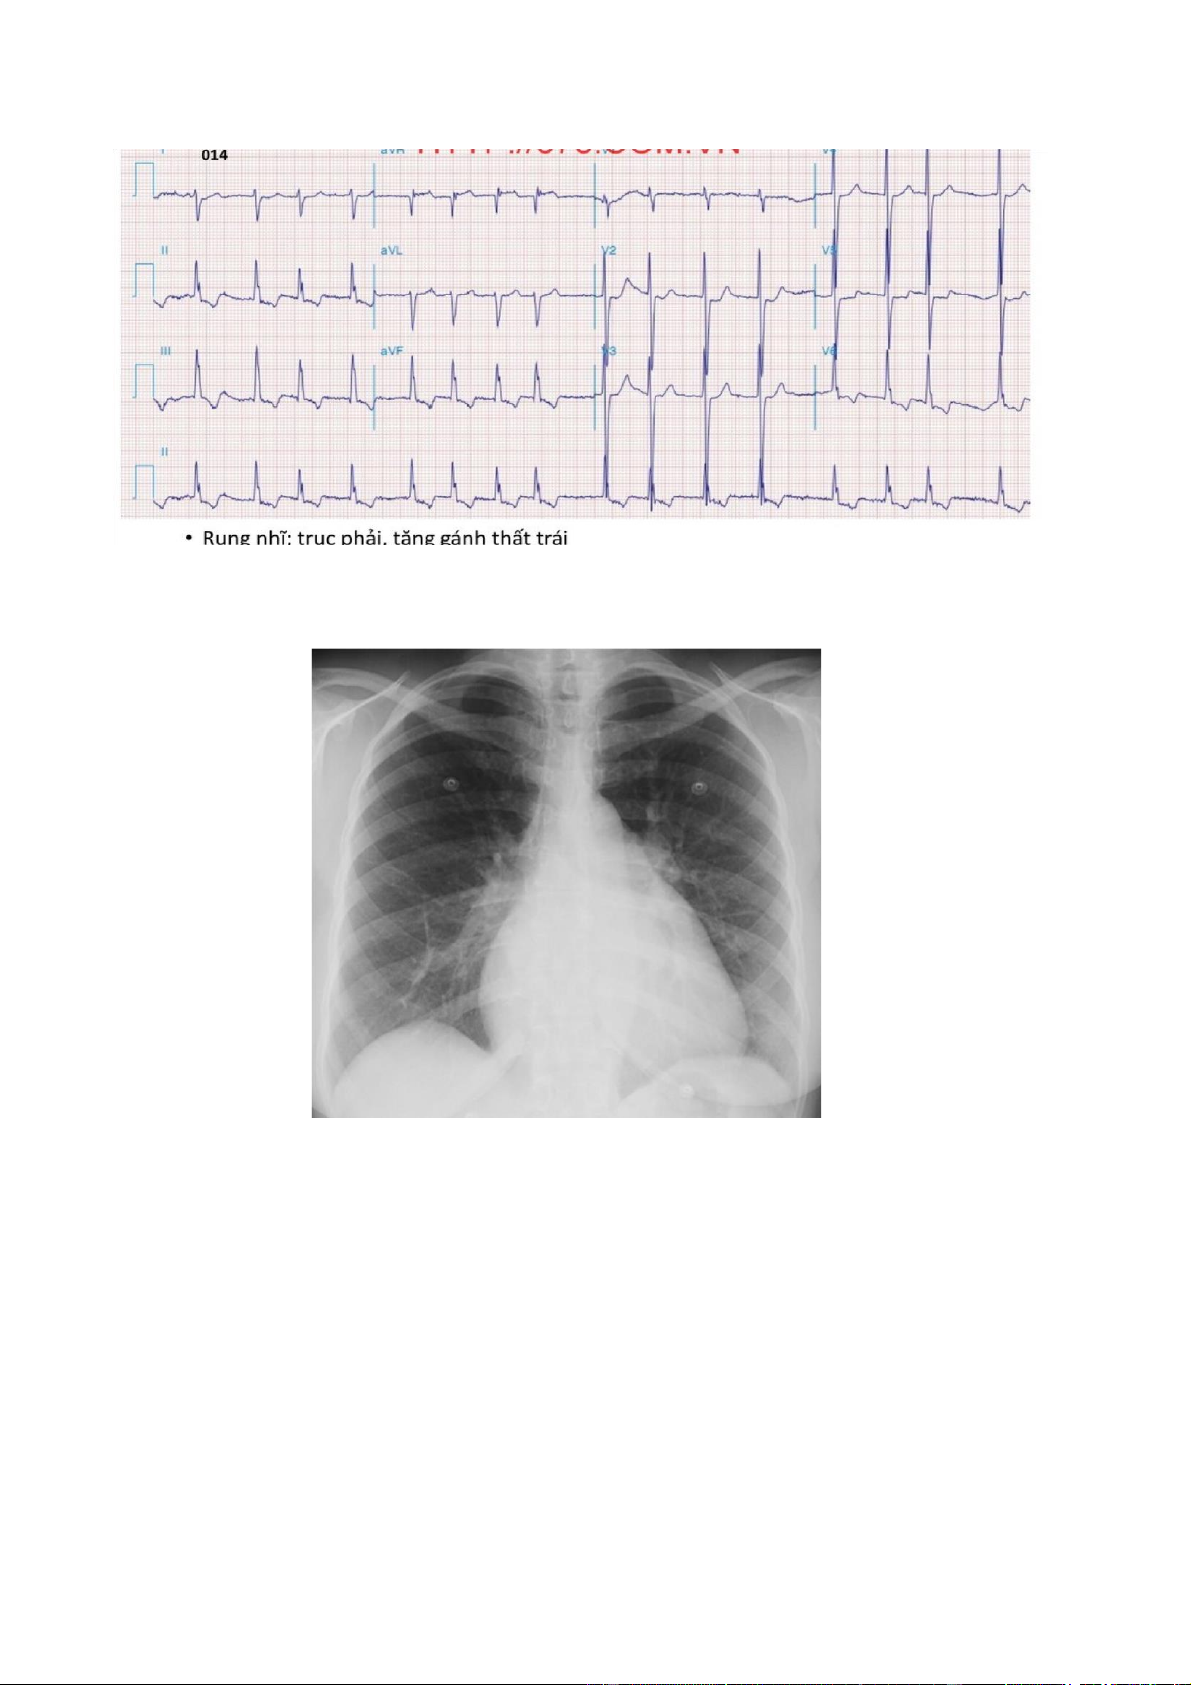

+ Gan dưới bờ sườn 3 cm, măt nhẵn, bờ tù, ấn tức.̣ + Cận lâm sàng: . Điện tim đồ: lOMoAR cPSD| 58490434

Hình 1. Hình ảnh điên tâm đồ của bệnh nhâṇ

. X quang tim phổi: kết quả ở hình 2.

Hình 2. Hình ảnh X quang của bênh nhâṇ